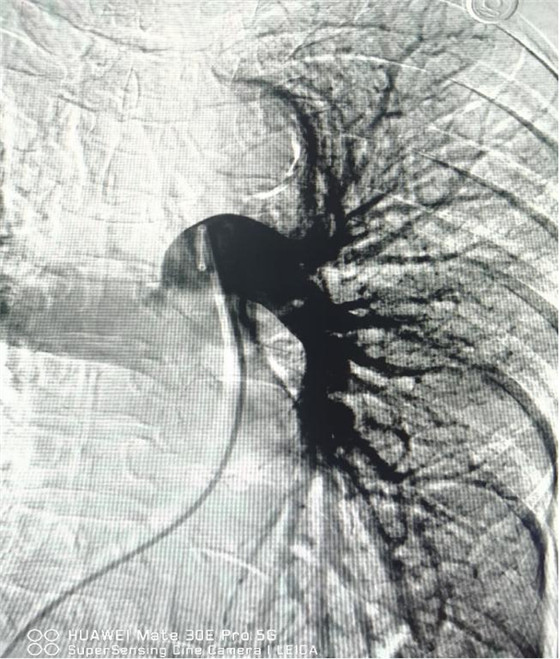

經(jīng)皮肺動(dòng)脈造影

經(jīng)皮肺動(dòng)脈栓塞導(dǎo)管碎栓溶栓術(shù)

經(jīng)綜合評(píng)估并與家屬充分溝通后,局麻下行肺動(dòng)脈造影,提示左肺動(dòng)脈主干及左肺下葉動(dòng)脈閉塞,立即予以經(jīng)皮肺動(dòng)脈栓塞導(dǎo)管介入碎栓溶栓術(shù)。在心內(nèi)科韋鋒主任、郭良玉主治醫(yī)師及成婷護(hù)師的默契配合下,爭(zhēng)分奪秒順利完成手術(shù)。術(shù)后即刻復(fù)查肺動(dòng)脈造影示左肺動(dòng)脈主干及左肺下葉動(dòng)脈恢復(fù)血流,生命體征穩(wěn)定,指脈氧恢復(fù)至100%。經(jīng)過(guò)精心治療與護(hù)理,目前患者已康復(fù)出院。